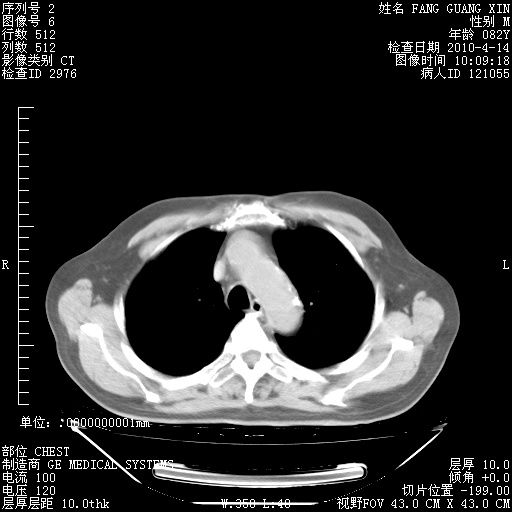

4月14日肺部CT

23.JPG

24.JPG

25.JPG

26.JPG

肺部CT平扫未见异常。